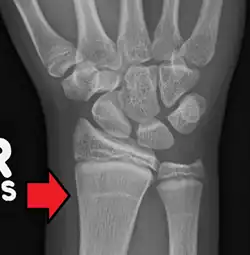

Harris-Linien

Harris-Linien sind Linien höherer Knochendichte, die im Röntgenbild erkennbar sind. Sie verlaufen parallel zur Epiphysenfuge in der Metaphyse langer Knochen – insbesondere des Schienbeines (Tibia) – und sind ein Zeichen für eine kurzzeitige Veränderung im Längenwachstum der Knochen. Im englischen Sprachraum sind die Bezeichnungen Harris lines, growth arrest lines, recovery lines, stress lines, Park-Harris growth arrest lines oder auch Park lines im Gebrauch. Der Name geht auf den Erstbeschreiber, den walisischen Anatomen Henry Albert Harris, zurück bzw. auf Edwards Albert Park (1877–1969).

Als Ursachen von Harris-Linien werden oft Vitamin- oder Nahrungsmangel (zum Beispiel bei Krankheit oder Unterernährung) oder längere Immobilität genannt; danach soll es nach Wachstumsstillständen zu einem folgenden Aufholwachstum mit einer veränderten Knochenneubildung kommen, die als quer verlaufender röntgendichter Streifen zu erkennen ist. Einmal angelegte Harris-Linien können rückgebildet werden und ihre Sichtbarkeit verlieren. Die Deutung von Harris-Linien als Anzeiger von Mangelernährung ist umstritten; neuere Studien legen dar, dass Harris-Linien nicht durch Mangelernährung entstehen, sondern eine wohl übliche Erscheinung beim Knochenwachstum von Kindern und Jugendlichen sind.